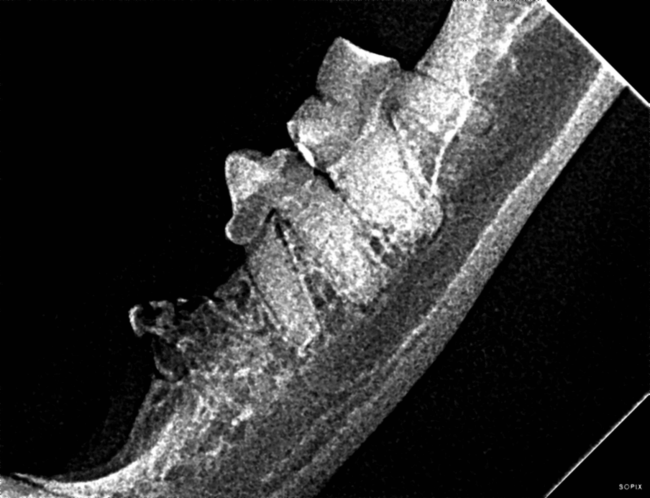

Les dents du lapin ne sont pas toutes directement visibles. Elles poussent en permanence. Les dents faciles à voir, situées sous le nez du lapin sont des incisives, qui servent à saisir et couper ses aliments. Elles poussent de 1 à 2 mm par semaine ! Le lapin possède également des molaires, avec lesquelles il mastique,…